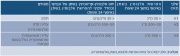

| 19:18, 2 במרץ 2016 | Bariatric4.png (קובץ) |  |

45 קילו־בייטים | Motyk | 1 | |

| 16:57, 29 בפברואר 2016 | Cdt2.png (קובץ) |  |

826 קילו־בייטים | Motyk | 1 | |

| 22:24, 28 בפברואר 2016 | Cdt1.png (קובץ) |  |

531 קילו־בייטים | Motyk | 1 | |

| 09:58, 28 בפברואר 2016 | Pthirus6.jpg (קובץ) |  |

374 קילו־בייטים | Motyk | 1 | |

| 09:58, 28 בפברואר 2016 | Pthirus5.gif (קובץ) |  |

86 קילו־בייטים | Motyk | 1 | |

| 09:57, 28 בפברואר 2016 | Pthirus4.jpg (קובץ) |  |

388 קילו־בייטים | Motyk | 1 | |

| 09:56, 28 בפברואר 2016 | Pthirus3.jpg (קובץ) |  |

383 קילו־בייטים | Motyk | 1 | |

| 09:56, 28 בפברואר 2016 | Pthirus2.jpg (קובץ) |  |

401 קילו־בייטים | Motyk | 1 | |

| 09:55, 28 בפברואר 2016 | Pthirus1.jpg (קובץ) |  |

662 קילו־בייטים | Motyk | 1 | |

| 09:50, 26 בפברואר 2016 | Iodine3.jpg (קובץ) |  |

2.4 מגה־בייטים | איל רובינשטוק | 2 | |

| 14:00, 23 בפברואר 2016 | Takeda777.png (קובץ) |  |

94 קילו־בייטים | דנה לוי | 1 | |

| 19:36, 22 בפברואר 2016 | Iodine2.jpg (קובץ) |  |

1.62 מגה־בייטים | איל רובינשטוק | 1 | |

| 19:28, 22 בפברואר 2016 | Iodine.jpg (קובץ) | שגיאה ביצירת תמונה ממוזערת: קובץ בגודל של יותר מ־12.5 מגה־פיקסלים |

3.45 מגה־בייטים | איל רובינשטוק | 1 | |

| 22:48, 21 בפברואר 2016 | בריאטרי1.jpg (קובץ) |  |

146 קילו־בייטים | Motyk | 1 | |

| 16:29, 21 בפברואר 2016 | CoverBeriatry.png (קובץ) |  |

246 קילו־בייטים | Motyk | 2 | |

| 09:51, 21 בפברואר 2016 | Shakuf.png (קובץ) |  |

110 קילו־בייטים | דנה לוי | 1 | |

| 12:14, 20 בפברואר 2016 | Tendons1.jpg (קובץ) |  |

412 קילו־בייטים | Motyk | 1 | |

| 15:45, 19 בפברואר 2016 | פרוקטוזאמין4.png (קובץ) |  |

17 קילו־בייטים | Motyk | 1 | |

| 15:34, 19 בפברואר 2016 | פרוקטוזאמין3.png (קובץ) |  |

16 קילו־בייטים | Motyk | 1 | |

| 15:14, 19 בפברואר 2016 | פרוקטוזאמין2.png (קובץ) | 2 קילו־בייטים | Motyk | 1 | ||

| 15:11, 19 בפברואר 2016 | פרוקטוזאמין1.png (קובץ) | 1 קילו־בייטים | Motyk | 1 | ||

| 11:51, 18 בפברואר 2016 | Prostate cancer1.jpg (קובץ) |  |

306 קילו־בייטים | Motyk | 1 | |

| 09:24, 17 בפברואר 2016 | Pre-diabetes3.jpg (קובץ) |  |

373 קילו־בייטים | Motyk | 1 | |

| 21:55, 16 בפברואר 2016 | Pre-diabetes2.jpg (קובץ) |  |

411 קילו־בייטים | Motyk | 1 | |

| 18:05, 16 בפברואר 2016 | Pre-diabetes1.jpg (קובץ) | 143 קילו־בייטים | Motyk | 1 | ||

| 10:33, 16 בפברואר 2016 | CKD3.jpg (קובץ) |  |

147 קילו־בייטים | Motyk | 1 | |

| 10:27, 16 בפברואר 2016 | CKD2.jpg (קובץ) |  |

207 קילו־בייטים | Motyk | 1 |